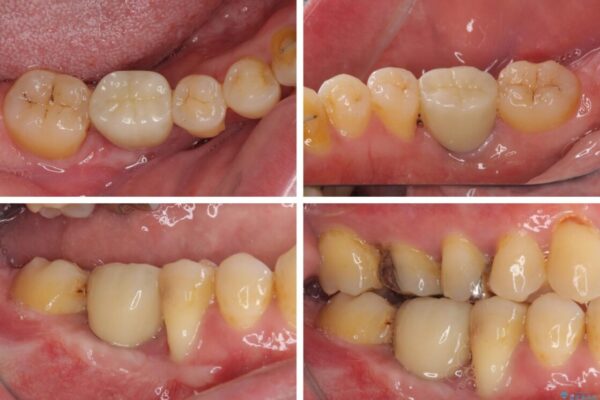

左右下顎の大臼歯は、ともに歯根が破折しており、抜歯が必要な状態でした。

放置したことで炎症による骨吸収が顕著であるため、骨造成を併用してインプラント埋入を行うこととしました。

治療前

• 割れてしまった奥歯とデコボコの前歯 矯正治療とインプラント治療 治療前画像